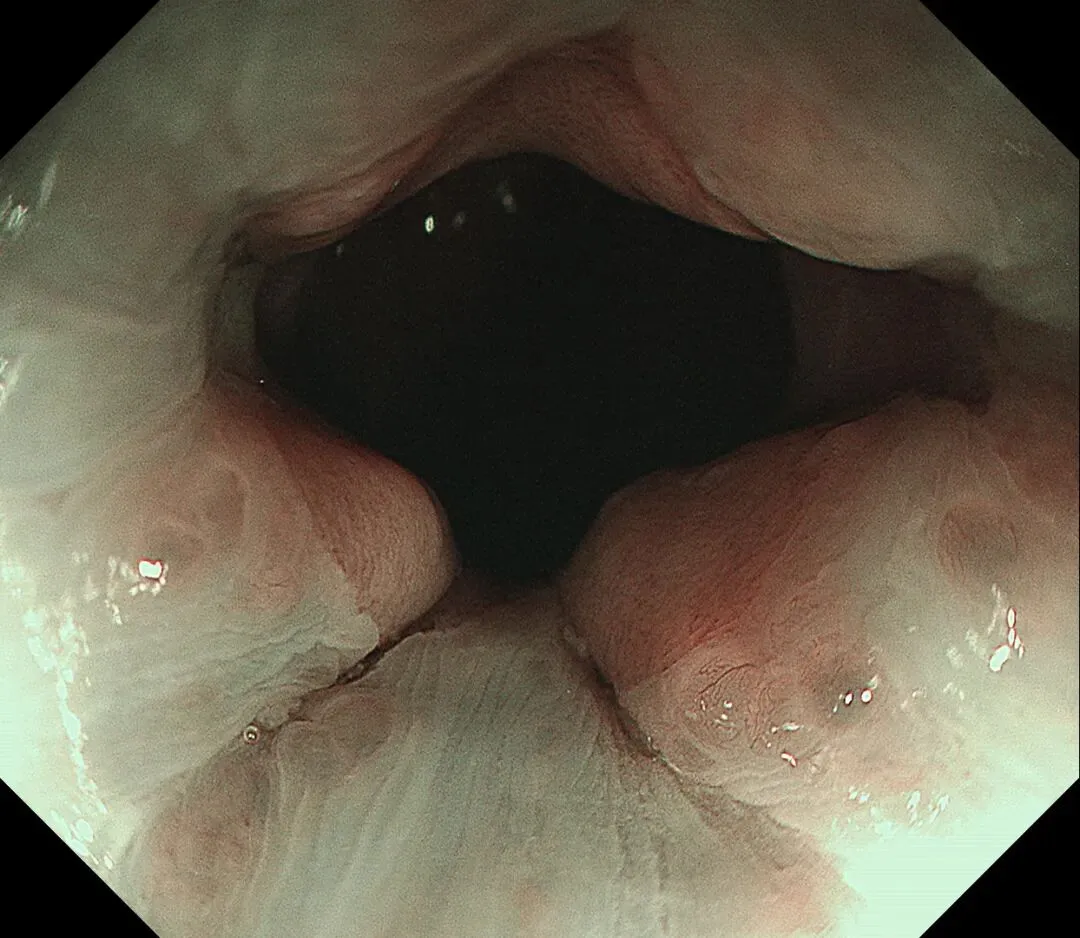

进镜至贲门观察到“花环征”,提示存在AIG的可能,带学生的内镜老师这个moment可以装一把,不过。。。偶尔也有翻车的时候,以下这例是在“Hp现症感染C3萎缩”患者的花环

有待进一步研究。。。